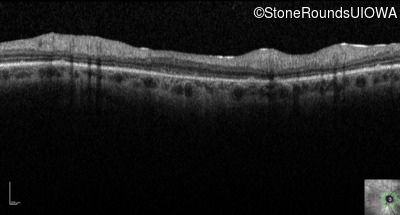

Optical Coherence Tomography - Right - 20/500

Exemplar / OCT Stack

OCT Stack

Optical Coherence Tomography - Left - 20/250